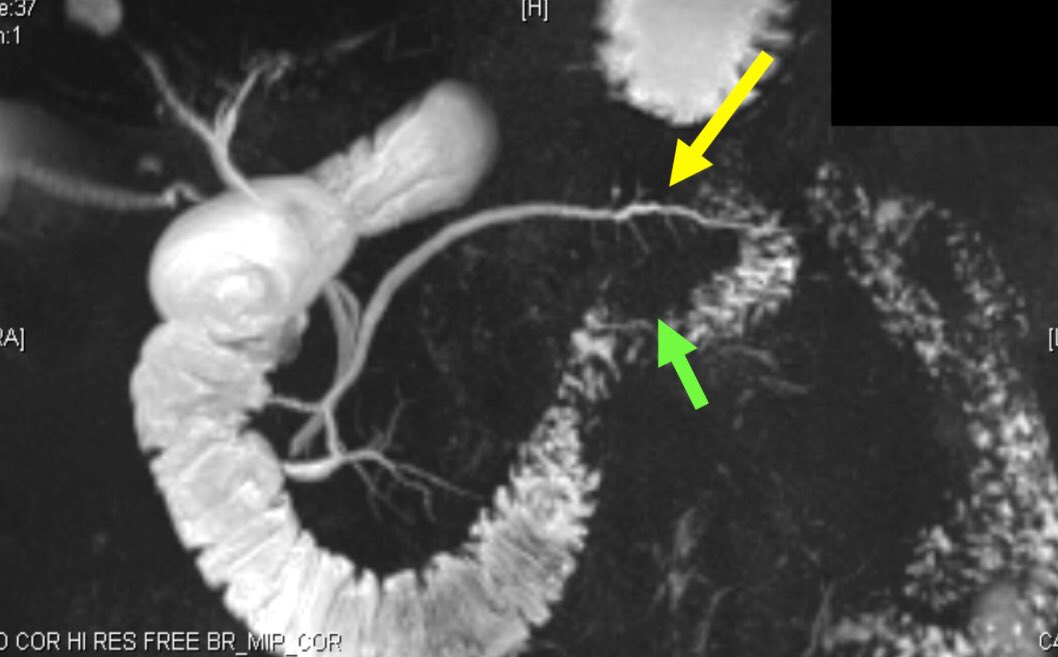

صورة مقطعية للبطن

CT scan

فحص اشعة فوق الصوتية

Ultrasound